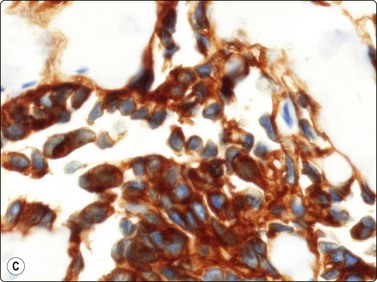

Tumors of vascular origin

Fine needle aspiration of hemangioma of any type yields plenty of venous blood. Smears may contain a few strands of endothelial cells with pale, spindly nuclei (Fig. 15.52). Macrophages, hemosiderin pigment and fibroblasts may be present if thrombosis has occurred. Most angiosarcomas are cutaneous tumors; only a minority are deep-seated. The cytologic features of angiosarcoma are variable. The cell population may be predominantly spindled, pleomorphic or epithelioid (Fig. 15.53A, B). A correct diagnosis is often not possible without immunocytochemical confirmation (CD31, CD34 and Fli-1) that the tumor cells are of endothelial origin (Fig. 15.53C). In epithelioid variants of angiosarcoma, EMA and keratin antibodies are often positive. The variable cytologic features in angiosarcoma have been described in several recent papers.65-67 Angiosarcoma of the breast is illustrated in Chapter 7 and of the spleen in Chapter 11.

image image image

Fig. 15.53 Angiosarcoma

(A) In this example, the smear population is predominantly of atypical spindle cells; differentiation from other spindle cell sarcomas requires immunostaining (H&E, LP); (B) Epithelioid pattern of gland-like cluster of malignant cells with rounded nuclei (MGG, HP); (C) A correct diagnosis is often not possible without immunocytochemical confirmation that the tumor cells are of endothelial origin (cell block, CD34, immunoperoxidase, HP).